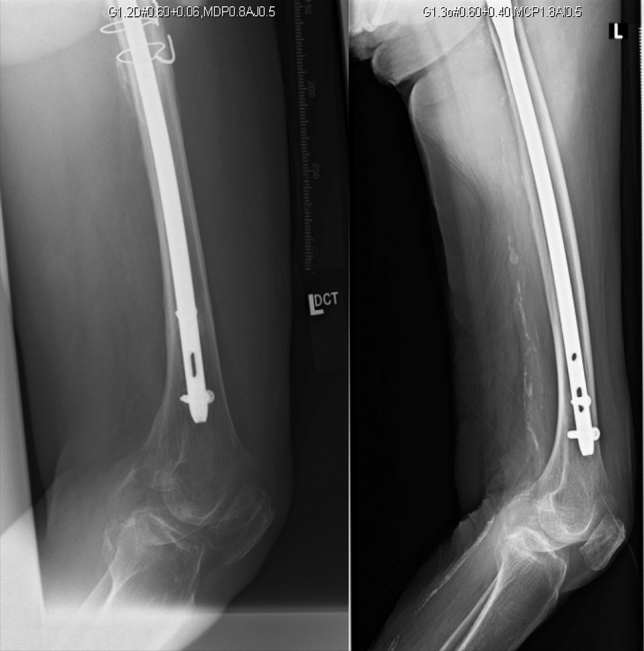

Fig. 1.

73/F who sustained an AO/OTA 31-A1 fracture which was fixed with a short TFNA + cement augmentation

A finding of note in using the TFN-A system was that in 4 out of 14 patients with cement augmentation, cement did not reach the tip of the head–neck element (or the superior half of the femoral head), and that most of the cement (about 70–80%) settled within the femoral neck (Fig. 1). All four of these cases used the helical blade for head–neck fixation. One possible explanation is that use of the helical blade resulted in further impaction of the cancellous bone around the tip of the blade, as it is intended to [8, 9, 15]. However, this denser bone then blocks the antegrade egress of the cement towards the tip of the blade. Instead the cement escapes via the path of less resistance, in a retrograde fashion towards the femoral neck. Earlier studies describing the use of cement augmentation have not described this phenomenon before [8, 9, 15]. Further in vitro studies can be conducted to test this hypothesis, as well as CT scan imaging of cement-augmented cephalo-medullary implants to analyse cement distribution in vivo. The authors are, however not discounting the possibility that these cases may just reflect a design flaw in the cement augmentation instrumentation of this new implant. Whether this phenomenon has an effect on the overall stability or failure rate of the construct, or the healing of the fracture is also an area that warrants further investigation.